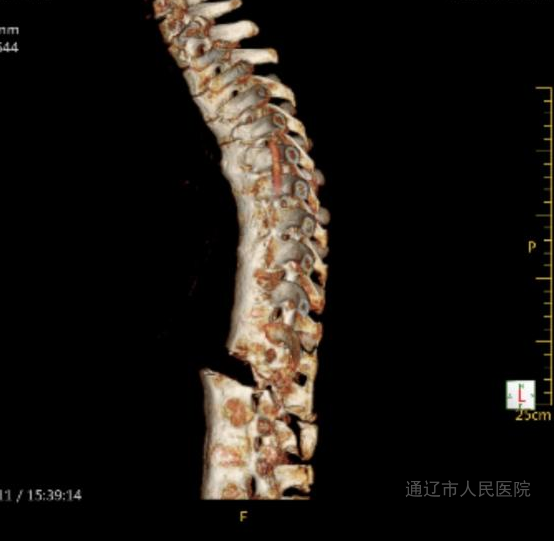

5月11日,43岁的患者包某某因强直性脊柱炎病史6年,身体状况不佳,又意外遭遇草料搅拌机绞伤胸腹部。伤后,患者随即出现腹痛、腰痛、呼吸困难等多种症状。紧急送医后,经检查确诊为左侧大量胸腔积液、少量腹腔积液、第1腰椎骨折伴滑脱,同时血压、血氧持续下降,病情极其危重,迅速被收入我院西院区急诊重症医学科(ICU)。